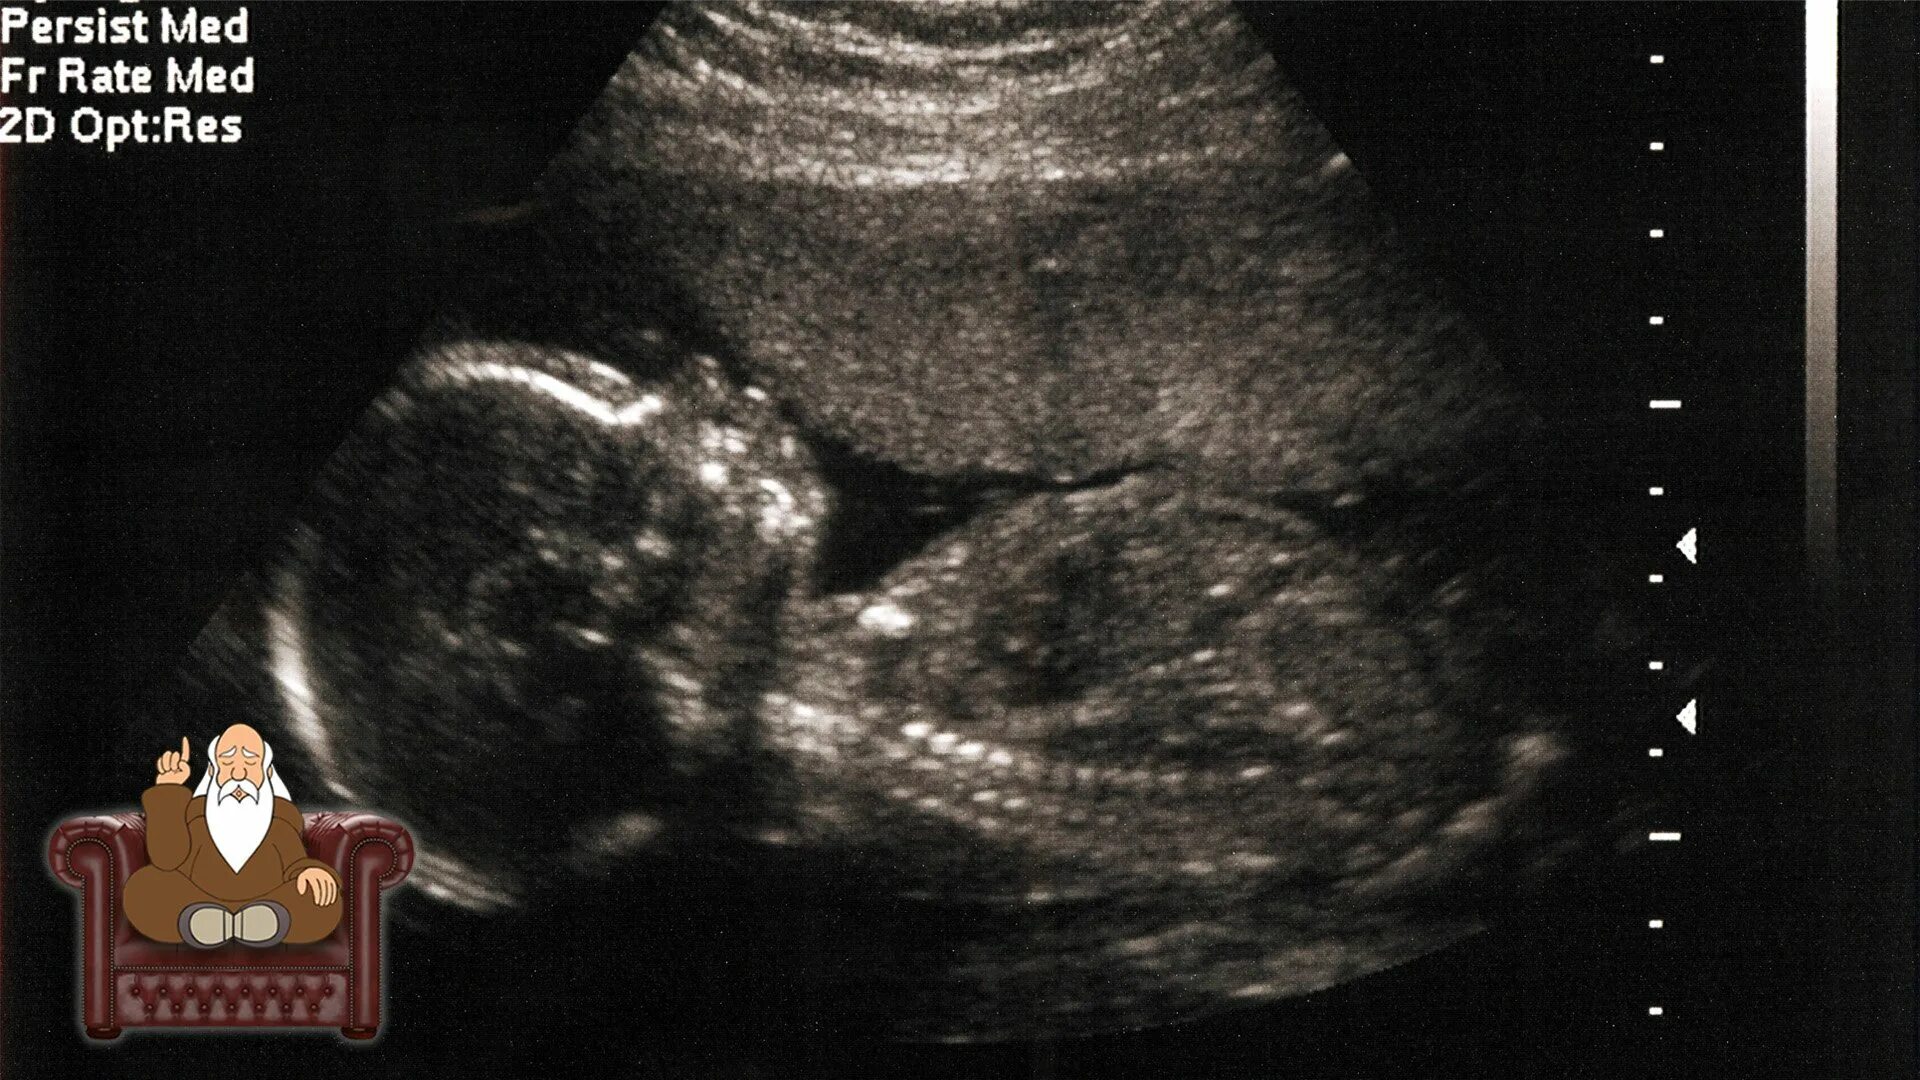

20 недель беременности ощущение